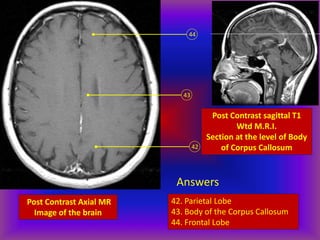

Post Contrast Axial MR

Image of the brain

42

43

44

Post Contrast sagittal T1

Wtd M.R.I.

Section at the level of Body

of Corpus Callosum

Answers

42. Parietal Lobe

43. Body of the Corpus Callosum

44. Frontal Lobe